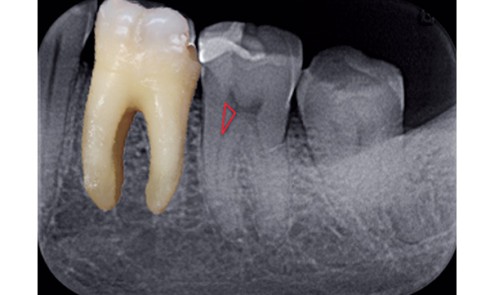

Article réservé à nos abonnés L’évasement coronaire du canal

Les instruments d’élargissement coronaire ont pour but de travailler à la jonction corono-radiculaire et de supprimer les contraintes initiales pour...